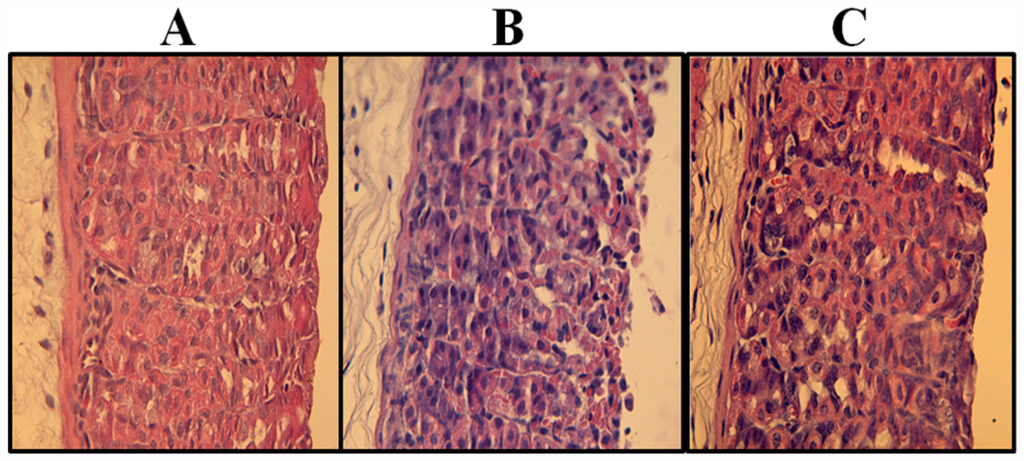

3.6. Histological Assessment

| Experimental group (n = 5) | Hemorrhagic damage (score, 0–4) | Edema (score, 0–4) | Epithelial cell loss (score, 0–3) | Inflammatory cells (score, 0–3) | Total (score, 0–14) |

|---|---|---|---|---|---|

| Saline | 0 | 0 (0–1) | 0 | 0 | 0 |

| Ethanol | 3 (3–4) | 3 (3–4) | 2 (2–3) | 0 (0–1) | 8 (6–10) |

| Ethanol + PLS 30 mg·kg−1 | 1 (0–2) * | 1 (0–1) * | 1 (0–1) * | 0 | 3 (0–3) * |